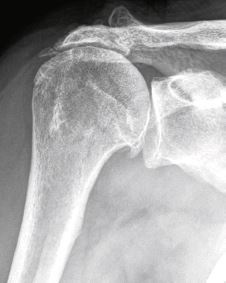

Das menschliche Schultergelenk zählt zu den Wundern der Natur aufgrund seiner ausgeprägten Beweglichkeit und Belastbarkeit. Vier Sehnen, welche als Gesamtheit als Rotatorenmanschette bezeichnet werden, sorgen für die reibungslose Funktion. Sie verbinden den Oberarmkopf mit der Schulterpfanne und sind sozusagen die Schaltzentrale des Gelenks. Eine Verletzung einer oder mehrerer dieser Sehnen kann die Schulter aus der Balance werfen und hartnäckige Schmerzen, besonders nachts, verursachen. Kraft- und Beweglichkeitsverlust sind weitere Symptome, die nach einem Unfallereignis oder bei längerem Bestehen mittels einer ärztlichen Untersuchung und bildgebender Verfahren wie Röntgen und MRI genauer abgeklärt werden sollten. Risse der Rotatorenmanschette (vgl. Abb. 1) sind in jüngeren Jahren meist unfallbedingt, während mit fortschreitendem Alter die Komponente der Abnützung an Bedeutung zunimmt.